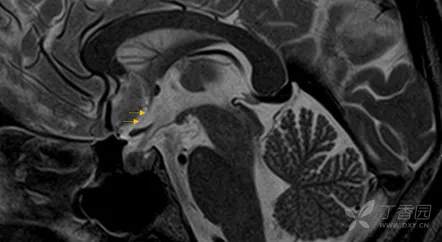

帆间池

帆间池 cistern of velum interpositum, 又称中间帆腔或第三脑室上池,位于第三脑室顶的上方、穹隆体和穹隆连合的下方。

冠状位示意图- CVI:前髓帆间隙,CC:胼胝体,ICV:大脑内静脉,F:穹窿,VL:侧脑室,T:丘脑,CN:尾状核,3V:第三脑室,CP:脉络丛。

它是一尖向前的三角区,两前外侧界为穹隆的内侧缘,后界为胼胝体压部。

此腔可经胼胝体压部的下方通大脑大静脉池。

在临床工作中,应注意帆间池与第三脑室顶部的区别:

1、帆间池的层面较高,第三脑室顶部层面较低;

2、帆间池后界是胼胝体压部,第三脑室顶部的后界为松果体;

3、帆间池为尖向前的三角区,不与侧脑室前角相连;而第三脑室前部为矢状位的狭长裂隙,前端可达侧脑室前角。